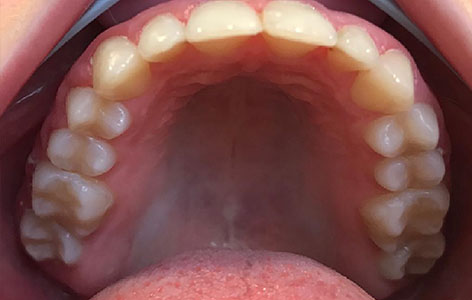

Disjunctorul

Este un aparat fix adițional, care este utilizat atunci când maxilarul este mult îngustat, rolul său fiind acela de a expansiona rapid arcada superioară pentru a face spațiu unor dinți sau pentru a corespunde cu arcada inferioară. Întotdeauna acest aparat este urmat de un aparat fix clasic care va continua alinierea dintilor in spatiul creat și definitivarea ocluziei corecte. Disjunctorul se cimentează pe molari si premolari, având partea activă reprezentată de un șurub median imediat sub bolta palatină.